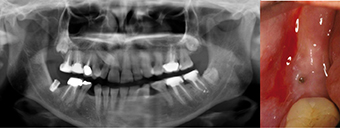

photo 1-

Cliché panoramique d’un homme de 30 ans. on observe les agénésies des prémolaires maxillaires, avec persistance des molaires lactéales 55 et 65 rhizalysées. Que ce soit au niveau osseux ou coronaire, les espaces disponibles sont insuffisants pour la mise en place de quatre prémolaires sur implants. un traitement d’orthodontie doit être envisagé.

photo 2-

Les aménagements orthodontiques aboutissent à la création des espaces requis, pour la mise en place de quatre implants en lieu et place des racines des prémolaires.

photo 3-

Le positionnement adéquat des implants dans l’espace édenté autorise la construction de couronnes transvissées directement dans les implants. ce type de construction permet de travailler les émergences de manière idéale, avec restitution d’un feston muqueux à la fois fonctionnel et cosmétique.

photo 4-

Cliché panoramique d’une femme de 45 ans qui demande le remplacement de la deuxième molaire mandibulaire droite (47) par une couronne sur implants. La patiente est adressée au spécialiste pour avis chirurgical et mise en place de la racine artificielle. Plusieurs autres dents sont absentes et non remplacées. Des déplacements dentaires conséquents sont observés, notamment les égressions des 16 et 17.

photo 5-

Un implant a été incorporé en 47 par le praticien, sans qu’aucune correction des malpositions soit envisagée. après ostéo-intégration, une couronne sera installée par l’omnipraticien.

photo 6-

Cinq ans après la mise en place de l’implant, la patiente retourne vers le chirurgien pour avis, suite aux dévissages récurrents de la couronne. un nouveau cliché panoramique permet de constater une perte sévère du niveau osseux autour de l’implant. La zone exprime du pus à la pression digitale.

photo 7-

L’observation clinique montre qu’aucun aménagement des espaces n’avait été mis en œuvre pour restaurer l’espace naturel de la couronne de 47. L’égression de 17 occupe la place de 47. La patiente a conservé les modèles de travail. La mise en place de la couronne sur ce modèle montre que la couronne de 47 n’est pas dans le plan d’occlusion adéquat. Ni la position du point de contact ni le profil des embrasures sont en conformité avec les exigences fonctionnelles et prophylactiques les plus élémentaires. La fracture de la céramique et le développement d’une péri-implantite en sont les conséquences inévitables.